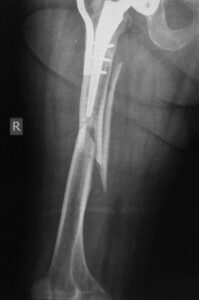

- Η ίδια ασθενής αντιμετωπίσθηκε σε άλλο κέντρο, δυστυχώς όχι με τον καλύτερο τρόπο.

- Αποτέλεσμα της καθυστερημένης πώρωσης ήταν ο λυγισμός της πλάκας και η συνολική αστοχία του συστήματος οστεοσύνθεσης.

- Η εικόνα του υλικού , ισχυρού μεν , αλλά σε περίπτωση που η πώρωση δεν ευοδωθεί, πάντα η κατάληξη θα είναι αποτυχία.

- H εικόνα του μηρού της ασθενούς με την λυγισμένη πλάκα και την απόκλιση του επιμήκη άξονα του μέλους.

- Η τελική οστεοσύνθεση που πραγματοποιήθηκε στο κέντρο μας με ειδική πλάκα τιτανίου από τους μηριαίους κονδύλους μέχρι τον ελάσσονα τροχαντήρα, αλληλοεπικάλυψη των υλικών χωρίς τη δημιουργία υψηλών συγκεντρώσεων φορτίων (stress risers). Επίσης έγινε βιολογική ενίσχυση του κατάγματος.